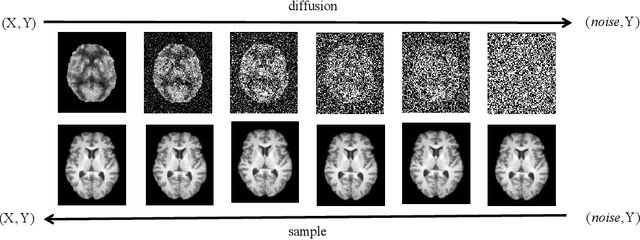

Abstract:MRI and PET are crucial diagnostic tools for brain diseases, as they provide complementary information on brain structure and function. However, PET scanning is costly and involves radioactive exposure, resulting in a lack of PET. Moreover, simultaneous PET and MRI at ultra-high-field are currently hardly infeasible. Ultra-high-field imaging has unquestionably proven valuable in both clinical and academic settings, especially in the field of cognitive neuroimaging. These motivate us to propose a method for synthetic PET from high-filed MRI and ultra-high-field MRI. From a statistical perspective, the joint probability distribution (JPD) is the most direct and fundamental means of portraying the correlation between PET and MRI. This paper proposes a novel joint diffusion attention model which has the joint probability distribution and attention strategy, named JDAM. JDAM has a diffusion process and a sampling process. The diffusion process involves the gradual diffusion of PET to Gaussian noise by adding Gaussian noise, while MRI remains fixed. JPD of MRI and noise-added PET was learned in the diffusion process. The sampling process is a predictor-corrector. PET images were generated from MRI by JPD of MRI and noise-added PET. The predictor is a reverse diffusion process and the corrector is Langevin dynamics. Experimental results on the public Alzheimer's Disease Neuroimaging Initiative (ADNI) dataset demonstrate that the proposed method outperforms state-of-the-art CycleGAN for high-field MRI (3T MRI). Finally, synthetic PET images from the ultra-high-field (5T MRI and 7T MRI) be attempted, providing a possibility for ultra-high-field PET-MRI imaging.